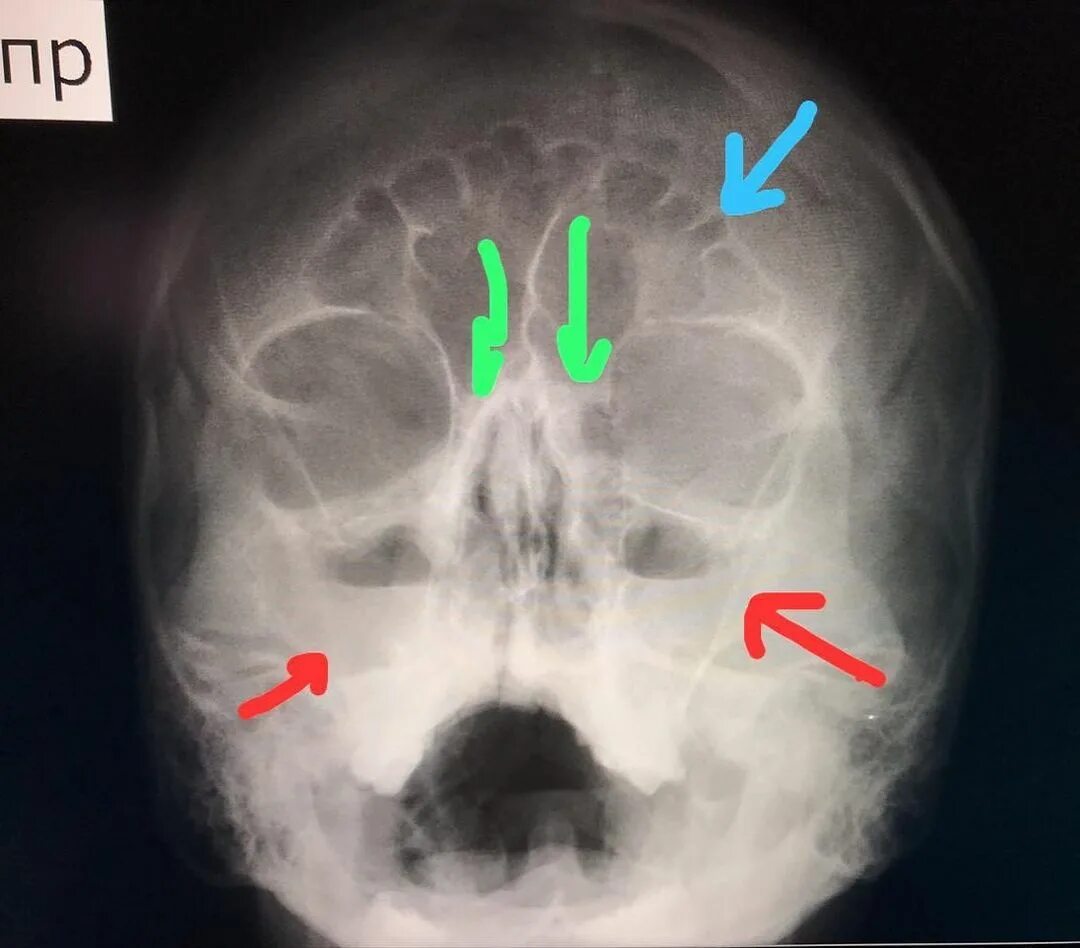

Двухсторонний верхнечелюстной синусит у ребенка